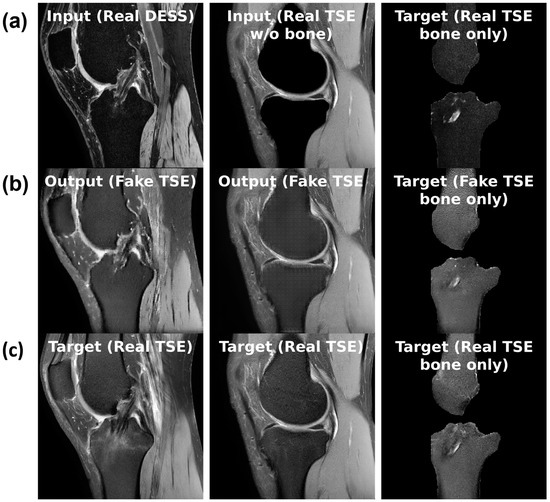

Figure 1. Left: original TSE image; right: TSE image with an overlay of BMEL annotations by two raters; Rater 2 marked the anterosuperior boundaries of the BMEL to extend further than Rater 1. TSE: turbo-spin echo.

As exemplified in Figure 1, these characteristics of BMELs may result in their expert annotations having poor intra- and inter-rater reliability. The poor reliability of the annotations poses a significant risk to any deep learning models trained on such unreliable targets, because the trained model will carry the biases and errors of the annotations when they learn to reproduce the segmentation masks. This is a fundamental challenge to supervised deep learning tasks, sometimes summarized as garbage in, garbage out. To the best of the authors’ knowledge, no research has been done to address the poor intra- and inter-rater reliability of BMEL annotations, nor to identify or quantify their extent, in the context of segmentation models and quantitative analysis.